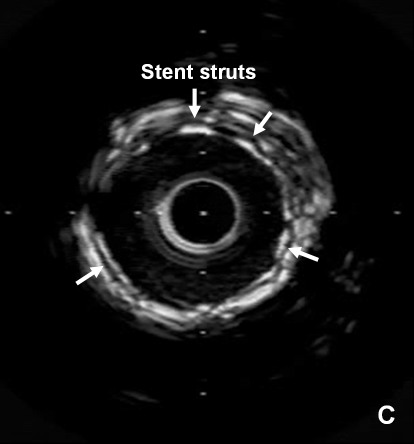

Likely in the majority of cases, this is due to lack of antiplatelet therapy . This is especially a concern in the perioperative period. Other reasons for stent thrombosis can lie with the stent itself, such as stent underexpansion or malapposition (acute or delayed). This would only be discerned by intravascular ultrasound or optical coherence tomography, which should be considered in all cases of stent thrombosis.